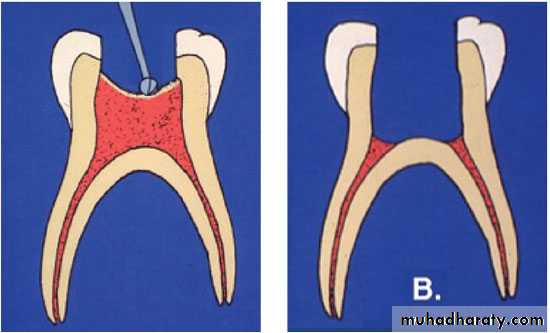

3- extirpation(to root out): removing the pulpal tissue after the pulpal opening.

4- debridement(removal of foreign or decayed matter): removing necrotic pulpal tissue and cleaning out the area.Root Canal Treatment

6- obturation(to close or stop up): filling and closing the canal area.